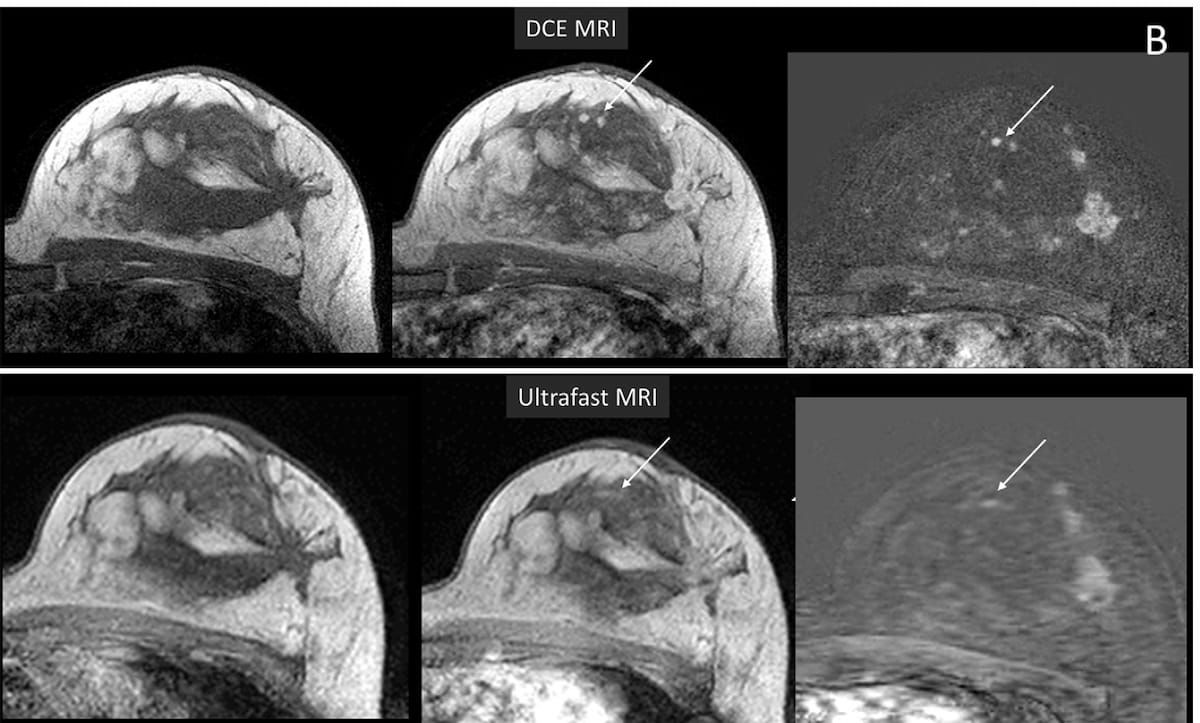

Study Questions Utility of Ultrafast Breast MRI for Challenging Lesions and Moderate/Marked BPE

Ultrafast breast magnetic resonance imaging (MRI) may have a variety of limitations in comparison to conventional dynamic-contrast-enhanced MRI (DCE MRI), according to new research. For the retrospective study, recently published in Radiology, researchers …